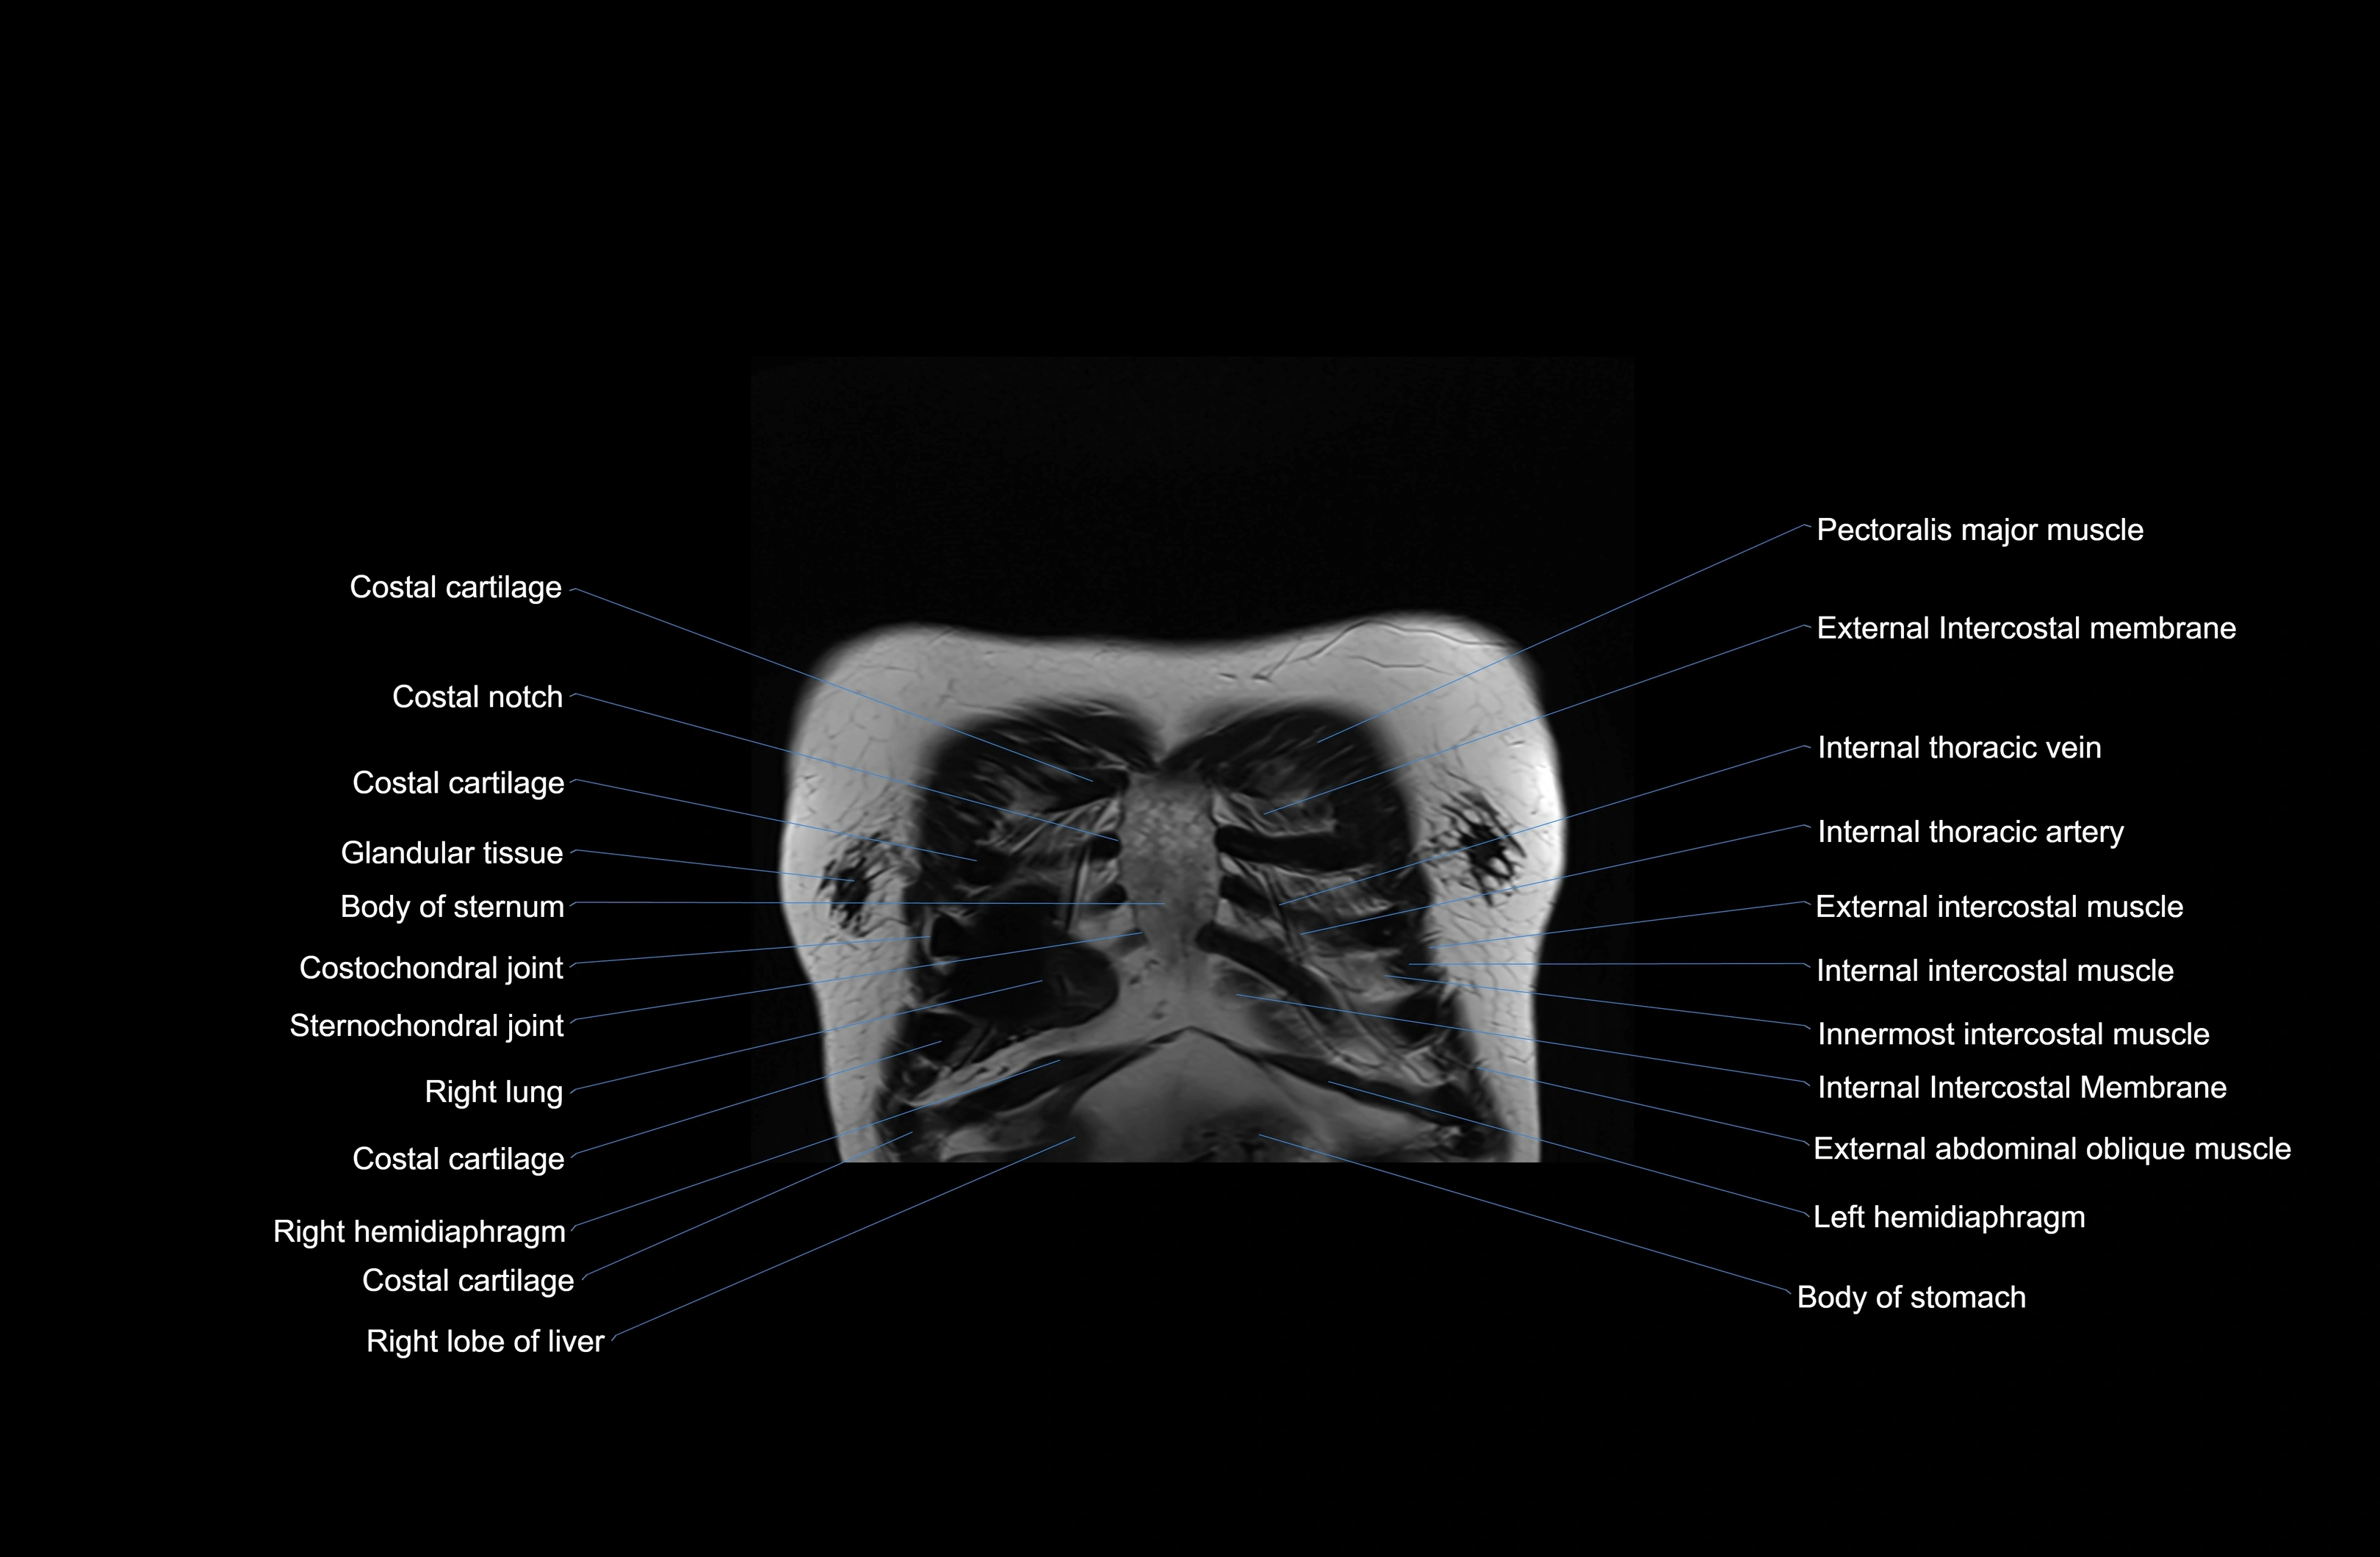

- Intercostal muscles

- Internal thoracic artery

- Internal thoracic veins